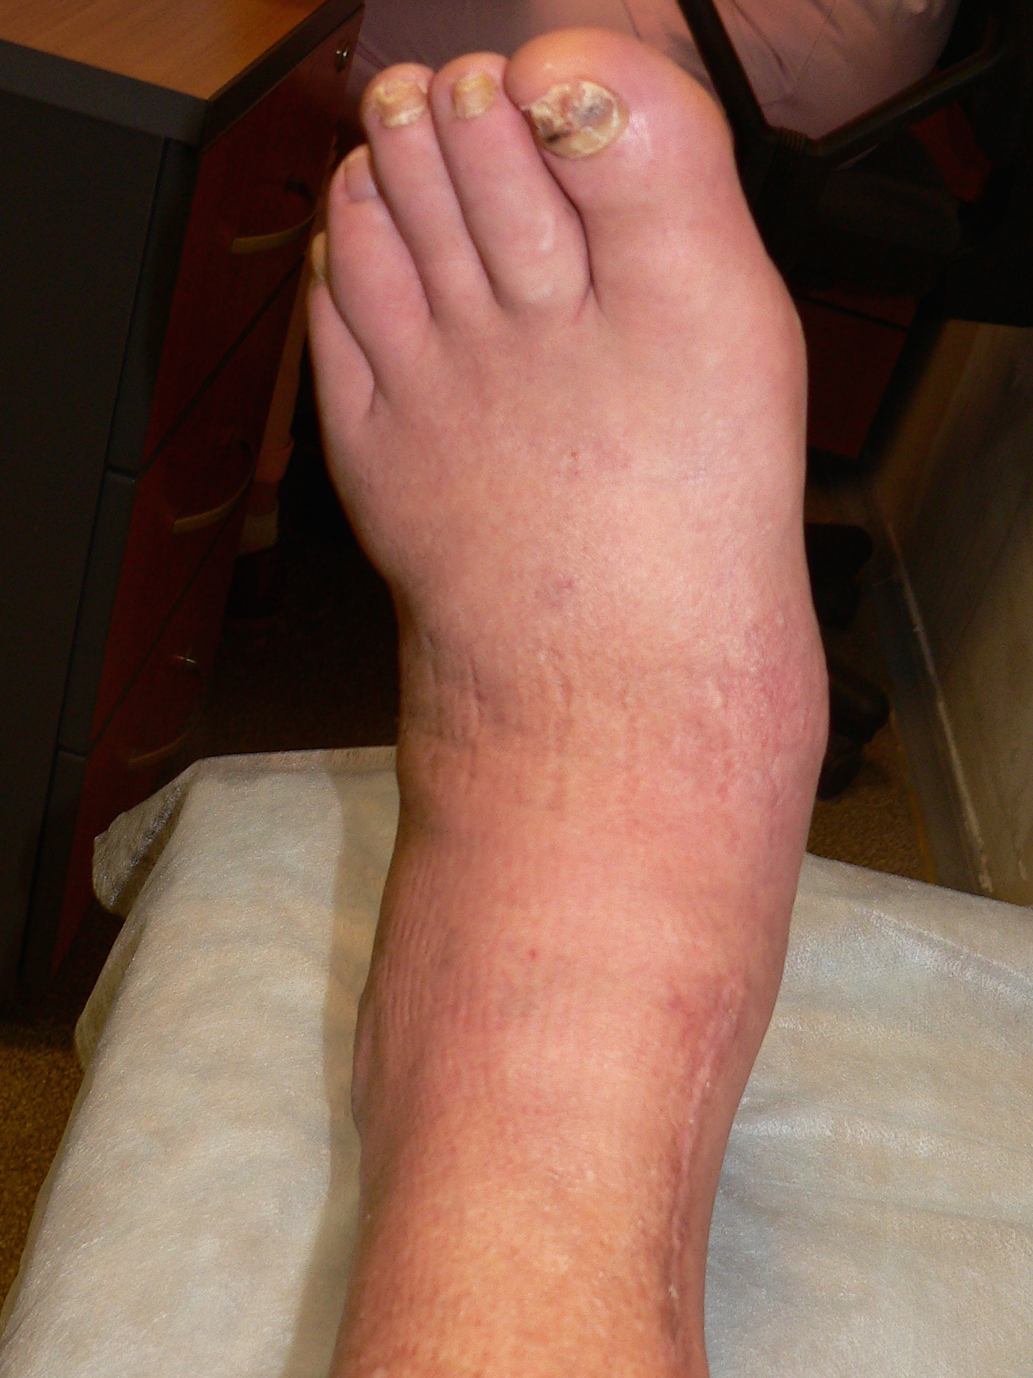

Передвигается при помощи костылей. На пораженную конечность не наступает.

Жалобы на умеренную боль при опоре на стопу и отечность левой нижней конечности. Рост 196 см, масса тела 125 кг. Определяются выраженный отек стопы и голени, легкая деформация медиального свода, отклонение оси стопы латерально по отношению к голени. Вибрационная, болевая, температурная чувствительность, ахилловы рефлексы отсутствуют, так же, как и чувствительность к 10-граммовому монофиламенту (балл по шкале НДСм=10). Пульс на артерии тыла стопы и на задней большеберцовой артерии не определяется. Температурный градиент +2,2°С в пользу левой стопы (рис. 4).

Рис. 4. Стопа пациента 2 при первом осмотре.

Последний осмотр – 21.01.2019 г. Сохраняется температурный градиент +2,2°С в пользу левой стопы. Отек конечности отсутствует. Гиперемии нет. Несмотря на иммобилизацию, деформация стопы усилилась (рис. 7).

Рис. 7. Стопа пациента 2 при осмотре 21.01.2019.